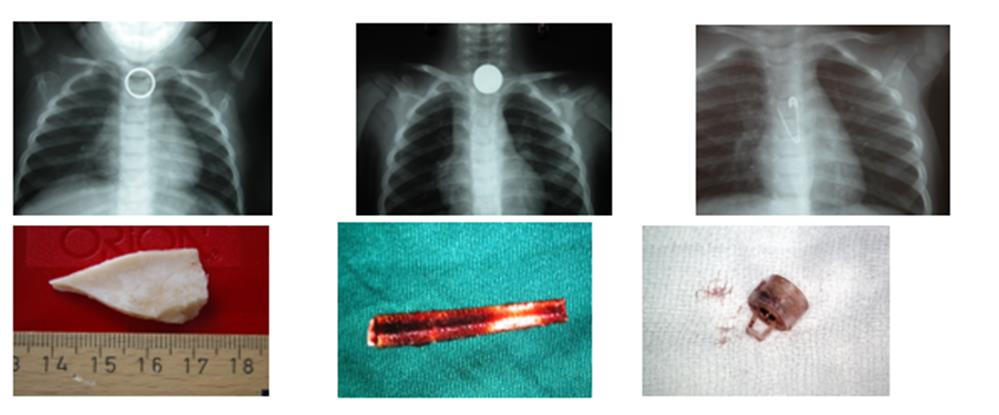

Οι εισροφήσεις ξένων σωμάτων σε παιδιά μέχρι 4 ετών, είναι δυστυχώς συχνές. Από μια μελέτη που έγινε από τις Παιδο-ωτορινολαρυγγολογικές κλινικές όλων των Δημόσιων Παιδιατρικών Νοσοκομείων της χώρας, από το 1995 έως το 2015, έγιναν 4.127 βρογχοσκοπήσεις για αφαίρεση ξένων σωμάτων του πνεύμονα σε παιδιά με εντυπωσιακή ποικιλία όσον αφορά και στο μέγεθος και στην υφή αυτών. Εικόνα 3.

(Εικόνα 3)